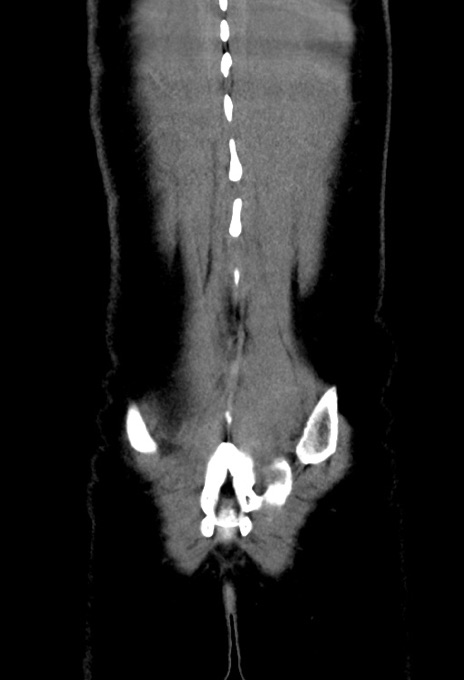

横断像

【症例】20歳代女性

【主訴】嘔吐、下腹部痛

【現病歴】昨日夕食後に嘔吐し下腹部痛が出現。本日になっても嘔吐持続し改善しないため来院。

【身体所見】意識清明、BT 37.2℃、BP 108/67mmHg、腹部:平坦、やや硬、下腹部正中から右にかけて圧痛あり、反跳痛軽度あり、tapping pain(+)。

【データ】WBC 13600、CRP 14.94